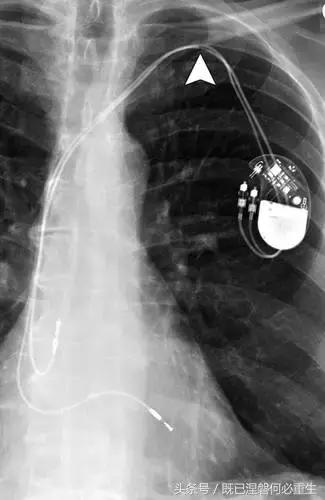

图。 7A 79岁的男性患有电极折断和迁移。

A,初始胸前X线片显示Pacesetter双腔起搏器低于锁骨的心房导线不完全断裂(变薄)(箭头)。